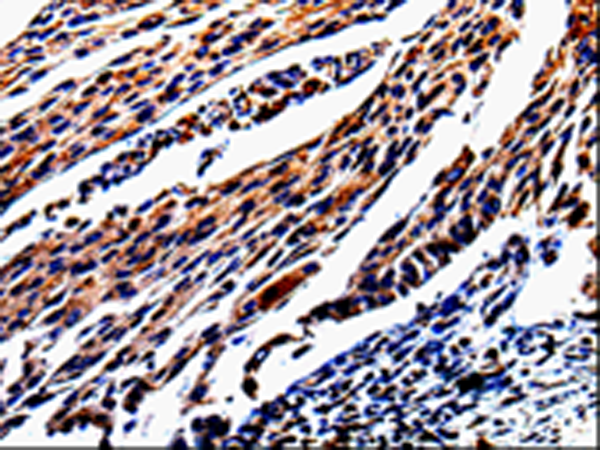

ELISA, IHC |

IHC positive control: |

Human cervical cancer and human lung cancer |

IHC Recommend dilution: |

25-50 |